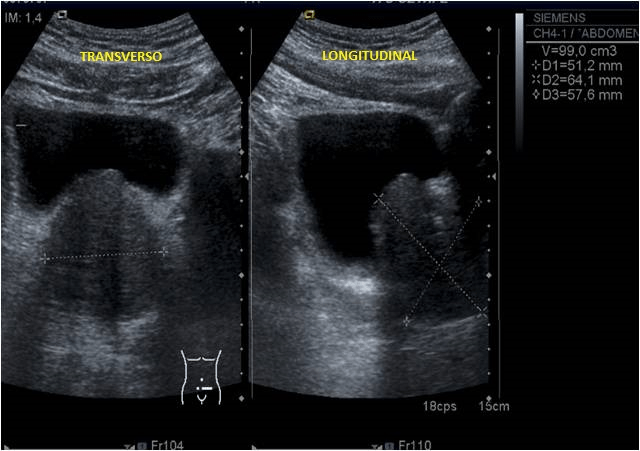

CÁLCULOS PROSTÁTICOS.

Las calcificaciones en la próstata son un hallazgo muy frecuente en la ecografía, pueden suceder a cualquier edad pero son más frecuentes en hombres a partir de los 50 años, llegando a aparecer hasta en un 75%.

Son las imágenes blancas con sombra negra que puedes identificar fácilmente en la foto.

También les llaman cálculos prostáticos y pueden formarse por acúmulo de material inorgánico en los pequeños conductos de la glándula, usualmente provienen de la propia secreción prostática o del reflujo de orina hacia la próstata que se produce en ocasiones. Sobre este material inorgánico se van depositanto las sales de calcio en el paso del tiempo, o como consecuancia y más aceleradamente, si hay alguna inflamación como una prostatitis.

En la mayoría de los casos las calcificaciones en la próstata son asintomáticas y se descubren casualmente al hacer una ecografía, radiografía o resonancia; durante una revisión urológica. Pueden aparecer en varones normales que nunca han tenido síntomas, o en pacientes diagnosticados de hiperplasia benigna de próstata (HBP), prostatitis crónica, cáncer de próstata o estenosis de uretra, y otras más.